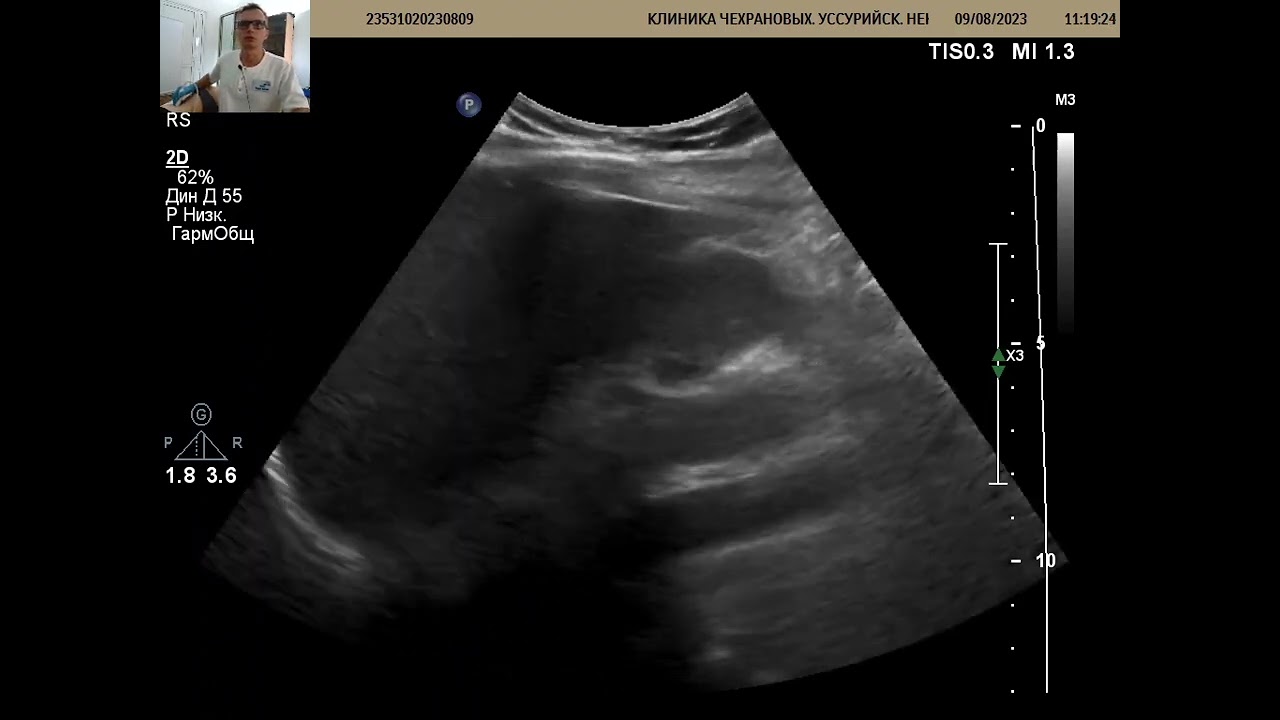

Результатом этого становится отображение на мониторе в графическом виде и с цветными фотографиями, на которых виден поток крови в кровеносных сосудах. Такая процедура позволяет изучить артерии изнутри в реальном времени и установить изменения кровотока в них. Причиной такого патологического состояния обычно становится тромбоз, спазм или сужение сосудов.

На кожу в той области, где будет проходить исследование, наносят специальный прозрачный гель, благодаря которому обеспечивается тесный контакт эпидермиса с датчиком. После этого специалист перемещает ультразвуковой датчик над исследуемыми областями, изучая при этом меняющиеся на мониторе изображения. Возможно появление необычных звуков, исходящих из УЗИ-аппарата. Причина их появления кроется в измерении потока крови, которая циркулирует в сосудах.

Ультразвуковая допплерография является одним из информативных способов оценки кровотока в средних и крупных сосудах. К такой процедуре прибегают для выявления различных патологий, определения показаний к хирургическому вмешательству на органе и для оценки эффективности проводимого лечения.